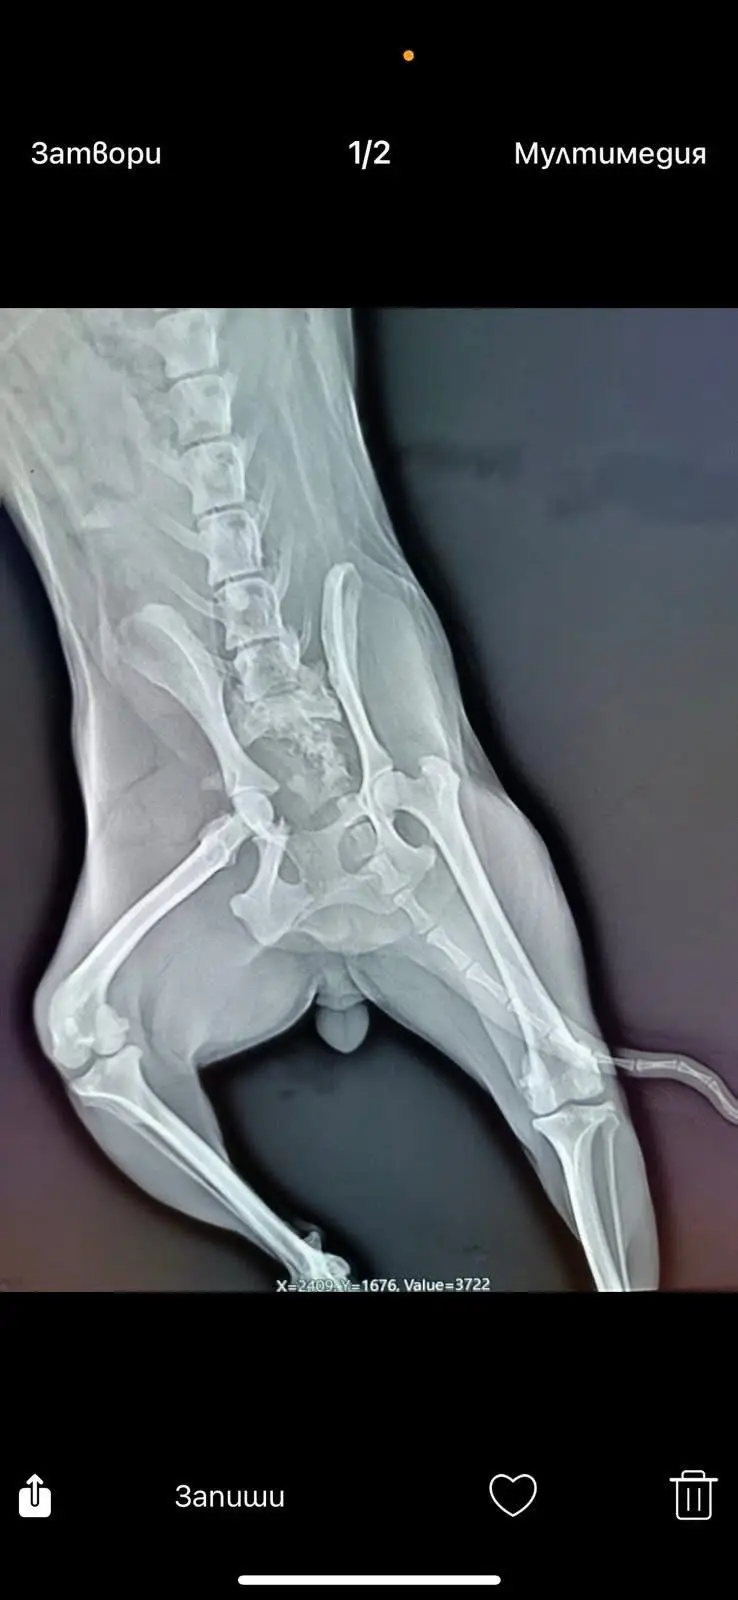

Намерено е блъснато пинчерче.

С тежки травми на гръбнака и таза. Уринира само, но към момента няма много апетит.Трябва и да предплатим операция и последващ престой на стойност около 1600 лв.

Без тази сума операцията няма как да се случи.

Времето работи срещу нея.